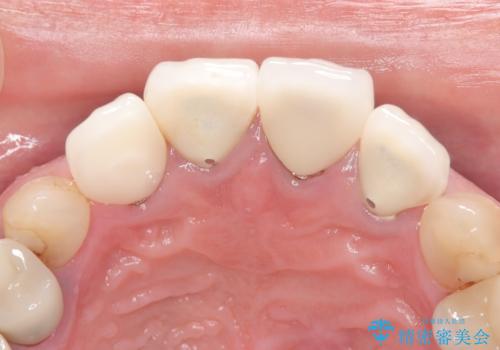

- 患者様は前歯の審美的な改善を希望されて来院されました。診査の結果、左上1の歯は過去の根管治療により歯根が破折していることが判明し、保存が難しい状態でした。そのため、**長期的な予後を考慮し、抜歯と同時にインプラントを埋入する「抜歯即時インプラント」**を計画。また、隣接する左上2の歯には感染が見られたため、歯根端切除術を同時に行い、感染の除去と治癒を促しました。右上1・2については、セラミッククラウンによる審美修復を行う方針としました。

左上1は抜歯と同時にインプラントを埋入し、骨や歯ぐきの形態を維持しながら治療を進めました。左上2は歯根端切除術により感染部位を除去し、保存治療を実施。右上1・2も含めた前歯4本をセラミッククラウンで修復し、自然な色調と形態を再現しました。治療後は、噛み合わせの安定とともに、美しく自然な前歯を回復することができました。患者様からも「見た目がとても自然で、自信を持って笑えるようになった」と喜びの声をいただきました。